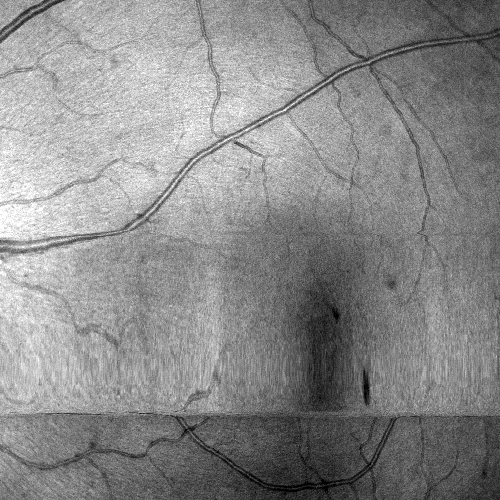

Images and estimated displacements are shown for a representative scan in Figureย 3. Tiny discontinuities prove absence of overregularization, and consistent transverse vibration indicates partial correction of ocular tremor. For quantitative analysis, we computed the median distance between the aligned A-scan displacements, and the fraction of displacements with a distance above 0.5 (problematic for supersampling) and 1 pixels (misalignments). The first and last 5% of B-scans were excluded, because they might not overlap with the orthogonal data, preventing registration. As the distributions are heavily skewed, we present box plots in Figureย 4. The three outliers in each direction in the right plot originate from the same subject, which is shown in supplementary Figureย 6. It is critical to note that the parameter density (B-scan rate 205 Hz) of the hermite splines is insufficient to fully correct ocular tremor (frequency up to 100 Hzย [16]). Therefore, this aperiodic, wave-like motion (amplitude 30โฒโฒ 1.6ย ยตm on the retinaย [16]) cannot be fully corrected, and neither is fully represented in the reproducibility error. In the transverse directions, this puts a lower accuracy limit on the evaluation scheme, but it is small compared to the pixel spacing (12ย ยตm). Using an Nvidia RTX 5000 GPU, the median and maximum runtime in the test set, excluding disk I/O which is irrelevant in clinical routine, was 8.6ย s and 31.3ย s. Tableย 1 compares average runtimes of various methods. Lastly, registration of individual B-scan repeats is demonstrated on a swept-source scanner in Figureย 5.